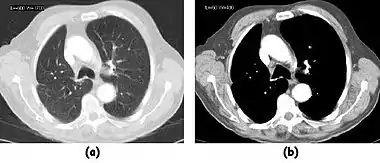

![]() Fig. 7.15.2: Effect of window width and level on CT image display: (a) Level = 50; Width = 200. (b) Level = 50; Width = 400. The image in (a) is displayed with greater contrast and appears noisier than that in (b). | ![]() Fig. 7.15.3: Effect of window width and level: (a) Level = -600; Width = 1700. (b) Level = -60; Width = 400. Image (a) displays the lung tissue more clearly, while image (b) can be used to highlight any pulmonary lesions. |

- Figure 7.15.3 illustrates the use of a relatively narrow window to highlight pathology in the lungs.